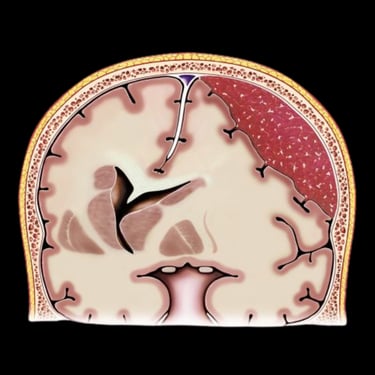

El hematoma subdural subagudo se caracteriza por la acumulación progresiva de sangre entre la duramadre y la superficie cerebral, generalmente posterior a un traumatismo craneal. Esta condición puede generar síntomas como dolor de cabeza persistente, confusión, debilidad en extremidades o alteración del estado de conciencia. El tratamiento quirúrgico consiste en la evacuación del hematoma mediante burr hole ampliado, técnica que permite realizar un orificio en el cráneo para drenar el contenido hemático y descomprimir el cerebro. Este procedimiento ayuda a disminuir la presión intracraneal, mejorar los síntomas neurológicos y prevenir complicaciones asociadas a la compresión cerebral.